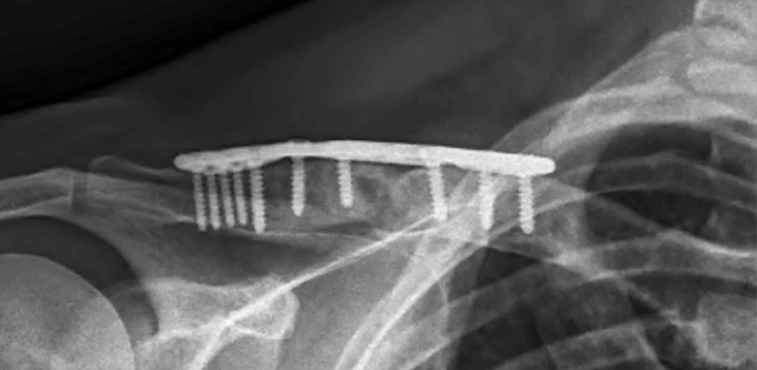

At six-month review, radiographs demonstrated solid fracture union with restoration of clavicular alignment. Clinically, he had achieved full range of motion, complete resolution of deformity, and was entirely pain-free.

Post op xray 2 of clavicle  open reduction and internal fixation of the right clavicle with iliac crest bone grafting

Post op xray 6 months

This case highlights the successful staged management of a chronic nonunion of the clavicle with iliac crest bone grafting. Through careful planning, meticulous surgical technique, restoration of clavicular length, rigid fixation, and autologous bone grafting, durable union and full functional recovery were achieved.